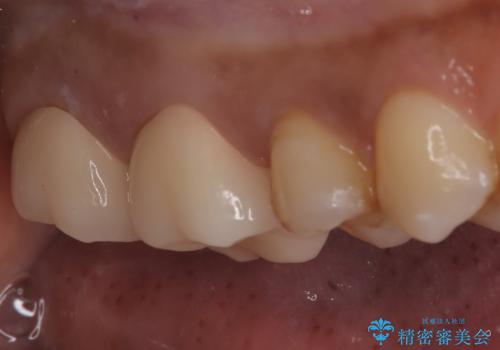

【オールセラミック】歯がズキズキ痛い。

- 左上の奥歯がズキズキ痛い、冷たいものも長引く痛みがあると来院されました。

根管治療を行った後にオールセラミッククラウンにて修復しております。